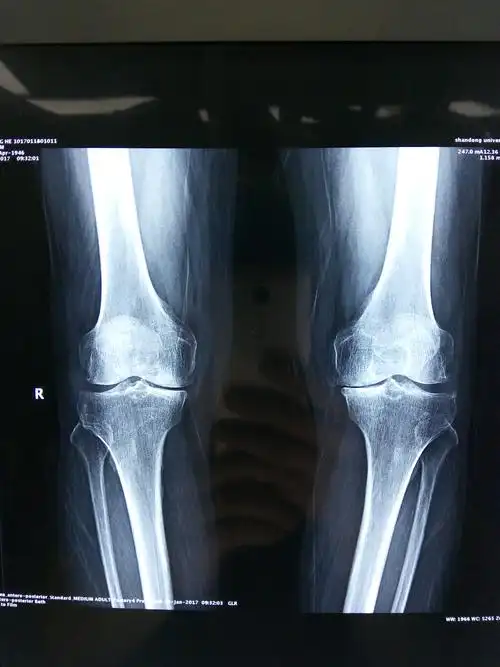

膝关节骨性关节炎行关节置换术